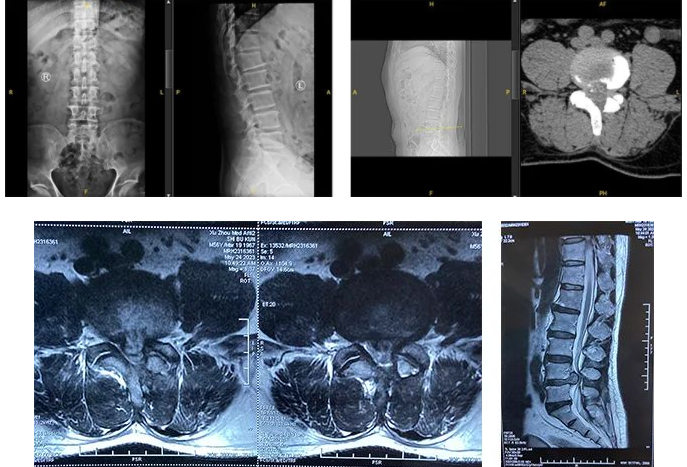

在sararz脊柱外科门诊,副主任医师孟磊为王先生做了系统性检查。结合腰椎MR显示其腰椎退行性变,L4/L5椎间盘明显向后脱出,硬膜囊及后方腰髓明显受压;L3/4、L5/S1椎间盘轻度膨出,最终诊断为腰椎管狭窄(L4/L5) 、腰椎间盘突出(L4/L5)。

术前